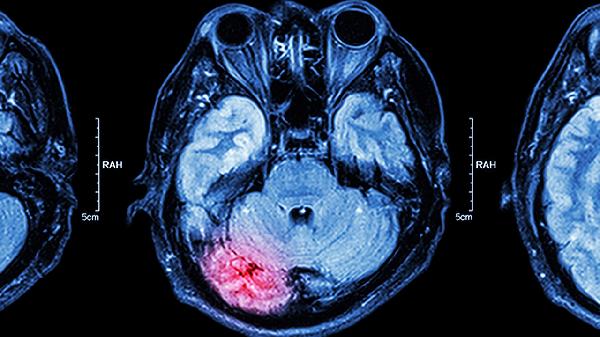

舒脑欣滴丸可用于脑外伤恢复期的头痛改善。头部外伤后可能遗留血管调节功能紊乱,导致慢性头痛、头晕。药物通过促进脑部血液循环,加速损伤修复。外伤后头痛患者常合并焦虑、失眠,必要时可联用谷维素片调节植物神经功能。恢复期间应避免剧烈运动,定期复查头颅CT观察恢复情况。